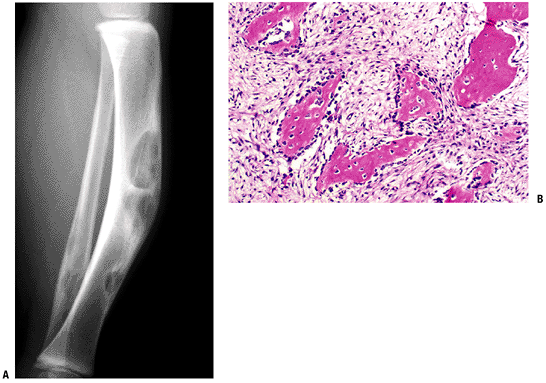

Pathology (Fig. 5.5-8)

Osteoblast-lined woven bone fragments separated by bland fibrous stroma

Zonal architecture with loose fibrous

tissue in the central zone, woven bone rimmed by osteoblasts in the

fibro-osseous zone, and lamellar bone in loose, fibrous, vascular

tissue in the peripheral zone

![]() |

Figure 5.5-8 Radiograph (A) and histopathologic specimen (B)

of osteofibrous dysplasia. Anterior intracortical tibial involvement is characteristic. Osteoblastic rimming is shown here as prominent, in contrast to fibrous dysplasia. |

Plain Radiographs (see Fig. 5.5-8)

Anterior intracortical involvement of middle third of tibia is classic.

Overlying cortex invariably thinned, expanded, or even missing

Sclerotic, geographic intramedullary border

Saw-toothed or soap-bubble, often multiple lucent areas anteriorly bordered by the deeper sclerotic border

No soft tissue extension or periosteal reaction